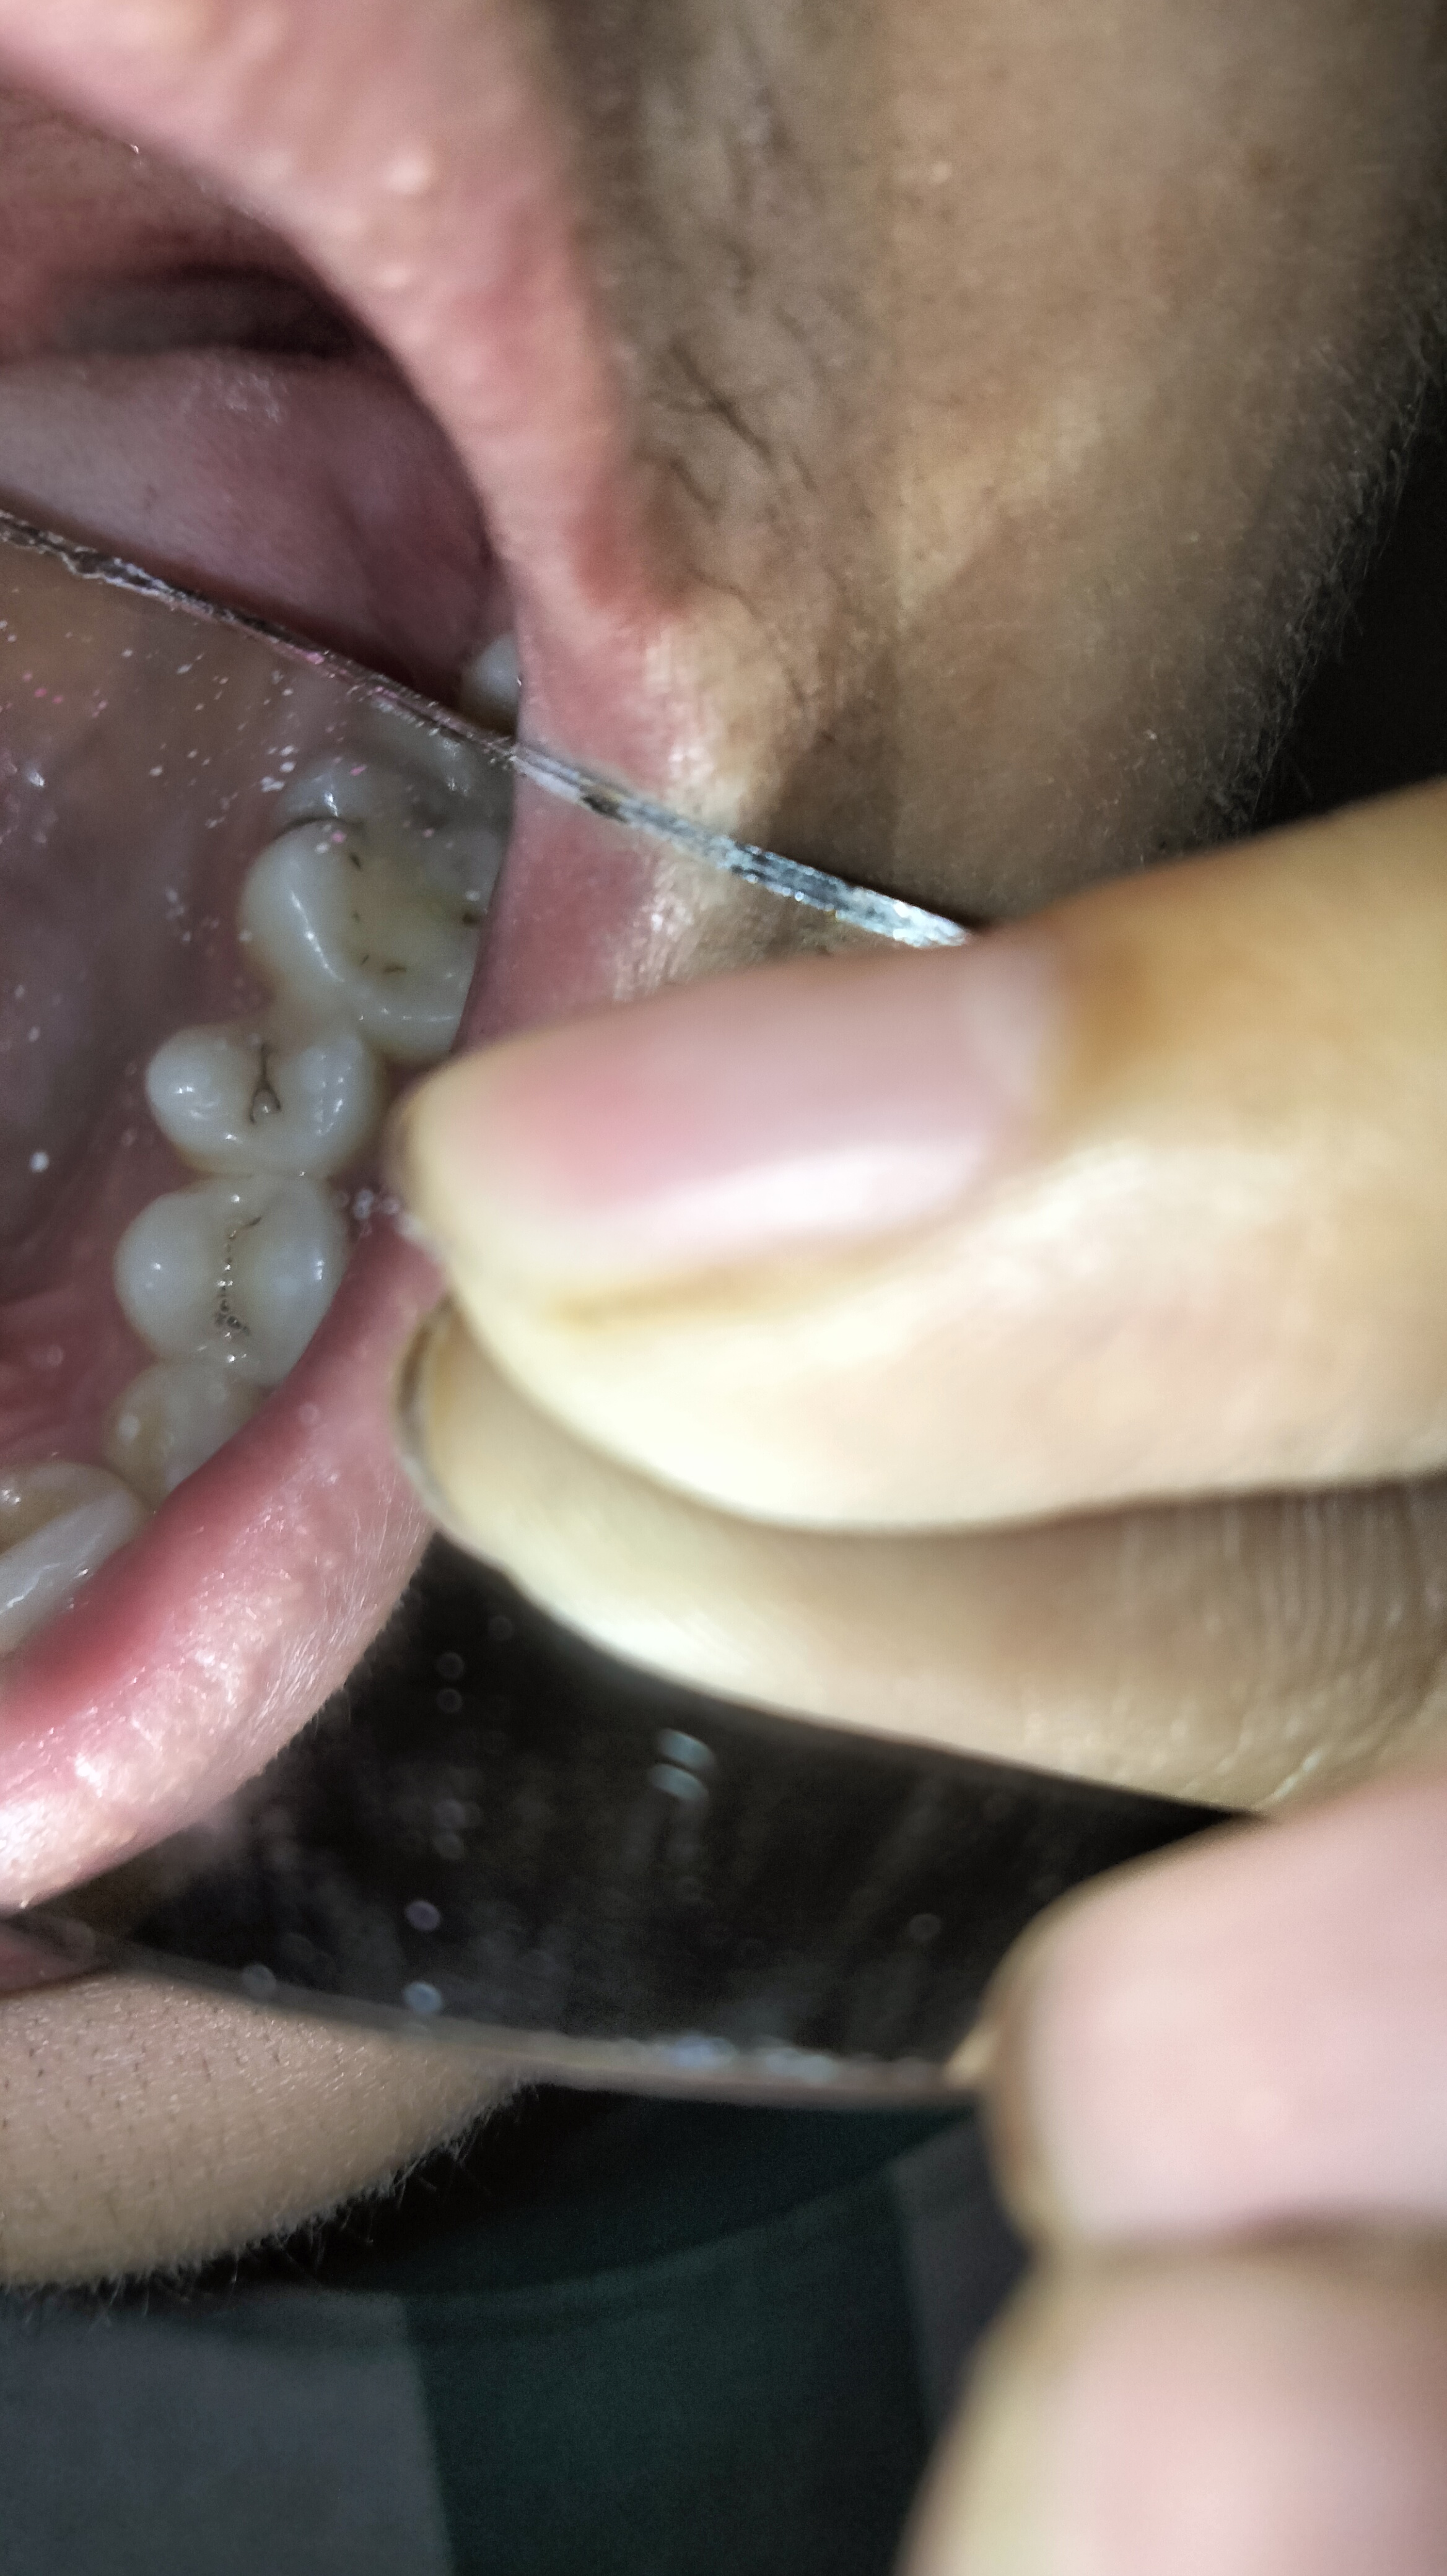

Bác sĩ ơi xem giúp em những cái này cái nào sâu cần trám và không cần ạ e đi khám thấy nói trám hết trơn 14 cái e lo quá giúp em với

Chào e. Chỉ răng có lỗ sâu mới cần trám. Còn sâu bề mặt ngà răng chưa trám nhé

Không trám hết đâu em. Em ra phòng khám răng để được khám tư vấn kỹ hơn

Dạ bác cho e hỏi 5 răng cửa của e có phải sâu không ạ

Đi họ bảo sâu 5 cái đó lun😭